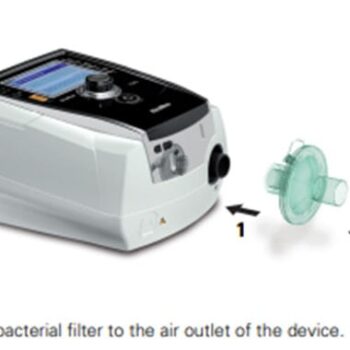

- פילטרים מקוריים למכשיר AirMini™ מבית ResMed.

- מונעים חדירת אבק, לכלוך וחלקיקים עדינים.

שמרו על איכות האוויר שאתם נושמים עם פילטרים מקוריים למכשיר AirMini™ מבית ResMed. הפילטרים תוכננו במיוחד כדי למנוע חדירת אבק, לכלוך וחלקיקים עדינים למכשיר ולדרכי הנשימה שלכם – וכך להבטיח טיפול יעיל ובטוח לאורך זמן.

פילטרים אלו הם חד-פעמיים ואינם ניתנים לשטיפה, מה שמבטיח היגיינה מרבית בכל שימוש. מומלץ להחליף את הפילטר אחת ל-4 עד 6 חודשים, או במידת הצורך, לשמירה על ביצועים מיטביים של המכשיר.